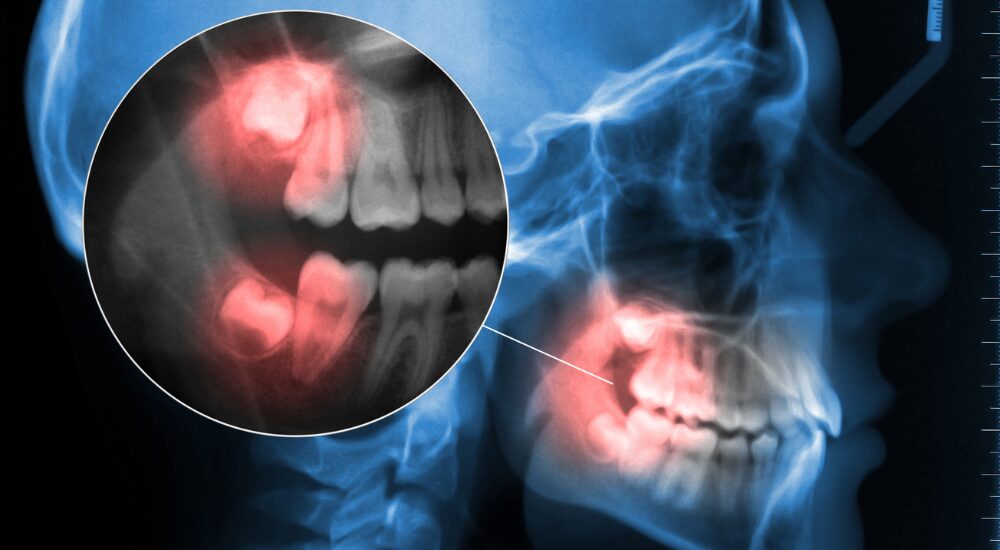

特に、複雑な抜歯(骨の中に埋まっている親知らずや、神経に近い位置にある歯の抜歯)については、他の歯科医院からご紹介いただき受診される患者さんも多くいらっしゃいます。

治療にあたっては、事前にCT撮影などによる正確な診断を行い、リスクを事前に把握したうえで安全性に配慮した処置を心がけています。

親知らずとは、福岡市でも多くの方が悩まされている歯の一つで、永久歯がすべて生えそろったあとに、一番奥に生えてくる「第三大臼歯」のことを指します。前歯から数えて8番目にあたり、「智歯(ちし)」とも呼ばれます。

一般的には10代後半から20歳前後に生えてきますが、個人差が大きく、まったく生えてこない方もいれば、骨の中に埋まったまま出てこない「埋伏(まいふく)歯」となる方もいます。

親知らずは、まっすぐ正しい方向に生えてくることが少なく、

• 横向きや斜めに生える

• 一部だけ歯ぐきから顔を出す

• 骨の中に埋まったまま出てこない

といったケースがよく見られます。

口腔内診査・レントゲン撮影を行います。親知らずの診察をしっかりと行います。通常のパノラマレントゲンを撮影した後に、必要な症例ではCT撮影を行います。